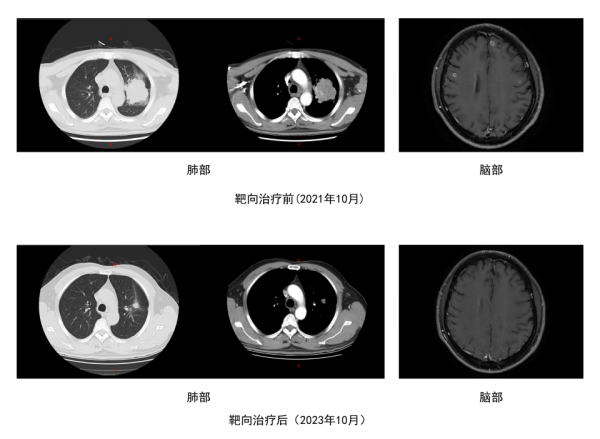

在我院就诊时,胸部 CT 像照妖镜般露出了 “元凶”—— 左肺上叶有个异常占位,头部 MRI 更发现了多个脑转移灶。进一步的肺穿刺活检和基因检测,最终确诊为 EGFR 19Del 及 TP53 突变的肺腺癌(IVB 期),已经是晚期肺癌,还合并了多发脑转移。这个结果对曾先生一家来说,无异于晴天霹雳,焦虑和无助瞬间笼罩了他们。

这种 “升级版” 靶向药堪称抗癌 “特警”,最厉害的本事是能突破血脑屏障,精准锁定并打击脑部的转移病灶。治疗刚满一个月,复查结果就让所有人松了口气:肺部病灶明显缩小,达到部分缓解(PR);脑转移灶更是彻底消失(CR)。整个治疗过程中,曾先生几乎没出现明显副作用,身体状况快速好转,生活质量直线上升,一家人重新看到了希望。